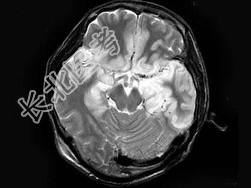

- 单项选择题男,46岁, 头痛、呕吐1周,MRI如图, 最可能的诊断是 ( )

A、脑梗死

B、病毒性脑炎

C、胶质瘤

D、化脓性脑炎

E、未见异常